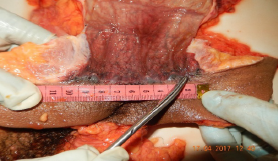

Tras la detallada aplicación de la exenteración pélvica total, el examen interno de las estructuras pélvicas reveló la presencia de diversas lesiones consistentes con violencia sexual severa. Los hallazgos principales en el canal vaginal y su periferia se resumen en la Tabla 1, mientras que las lesiones identificadas en la región anal se detallan en el la Tabla 2. Adicionalmente, se documentaron visualmente las siguientes lesiones, ilustradas en las figuras 15 y 16, que acompañan este caso.

a nivel de esfínter anal externo y equimosis en cara interna de recto

En un periodo de 11 años se efectuaron más de cien (100) EPT dentro de las autopsias medico legales, de los cuales se sospechaba agresión sexual, y que si bien en algunos casos mostraba lesiones visibles al examen externo en otras no se manifestaba lesiones en el área genital femenino y región anal, las edades de las cuales fueron sometidos a EPT fueron de 18 años en su rango menor y de 54 años en su rango mayor, con resección completa, de la cantidad total: 12 mujeres presentaban lesiones severas entre ellas hematomas, laceraciones, equimosis que comprometían toda la pared vaginal interna y el resto presentaba lesiones equimóticas, abrasiones comprometiendo región vaginal y región anal, que ponían de manifiesto la presencia de lesiones evidentes al examen macroscópico del perito forense, indicativos de agresión sexual.